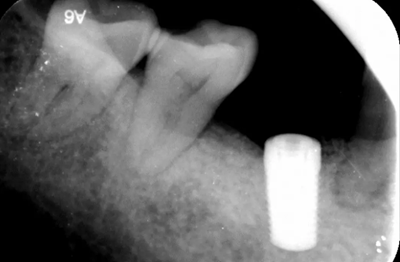

4、術(shù)前根尖片

3、術(shù)前全景片

46牙烤瓷冠修復(fù),根折伴大范圍骨吸收。(攝于2016年8月31日)